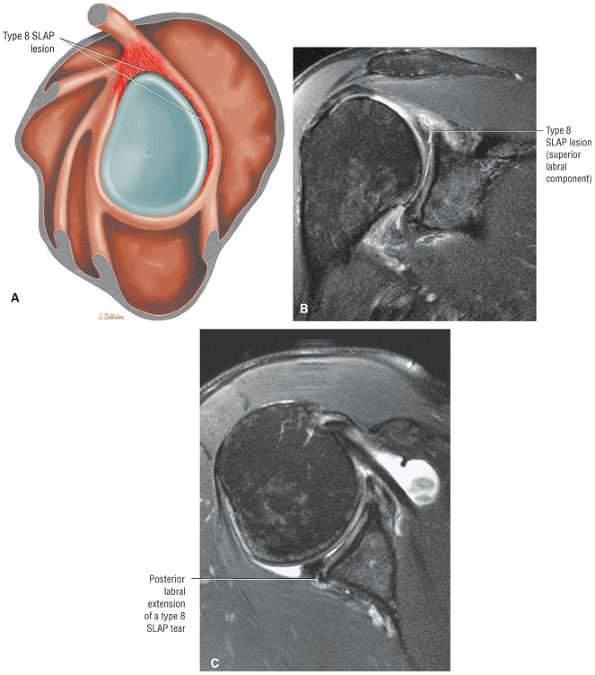

-

Impingement syndrome, a clinical diagnosis, is characterized by a range of MR findings from tendinosis to rotator cuff tears.

Intrinsic impingement is associated with shoulder instability.

Primary extrinsic impingement is associated with abrasion of the rotator cuff against the inferior surface of the acromion.